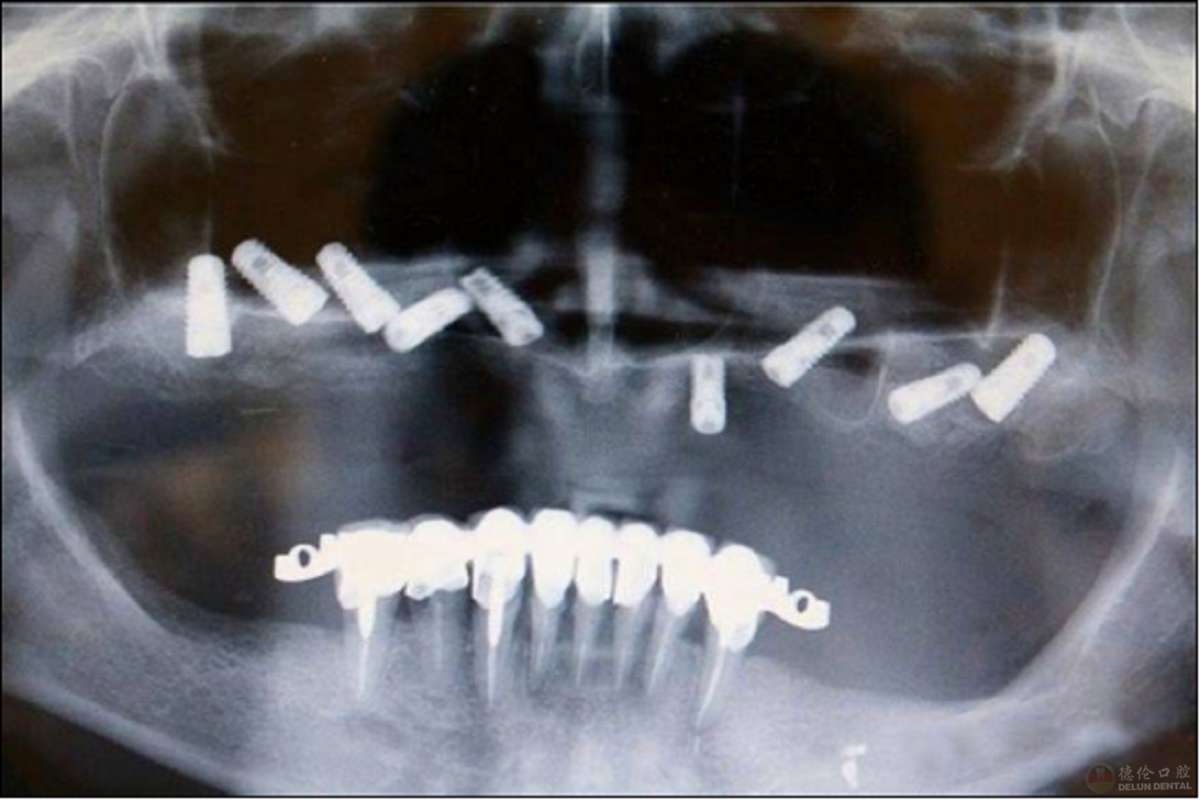

但是传统种植牙手术由于对口腔CT检测出来的数据缺乏相关计算机辅助设计和制造技术的支持,制定的方案也无法事进行数字化模拟。实际临床手术时没有有效仪器设备辅助,所有操作依靠医生个人经验以人工目测的方式确定人工牙根位置,以“盲种”进行种植牙,加大了手术风险。因此在传统种植牙手术中,由于植入位置、角度不准确而导致邻牙损伤、植体体受力不均等现象。

人工目测的“盲种”看上去很美,但是牙片却揭露了“真相”